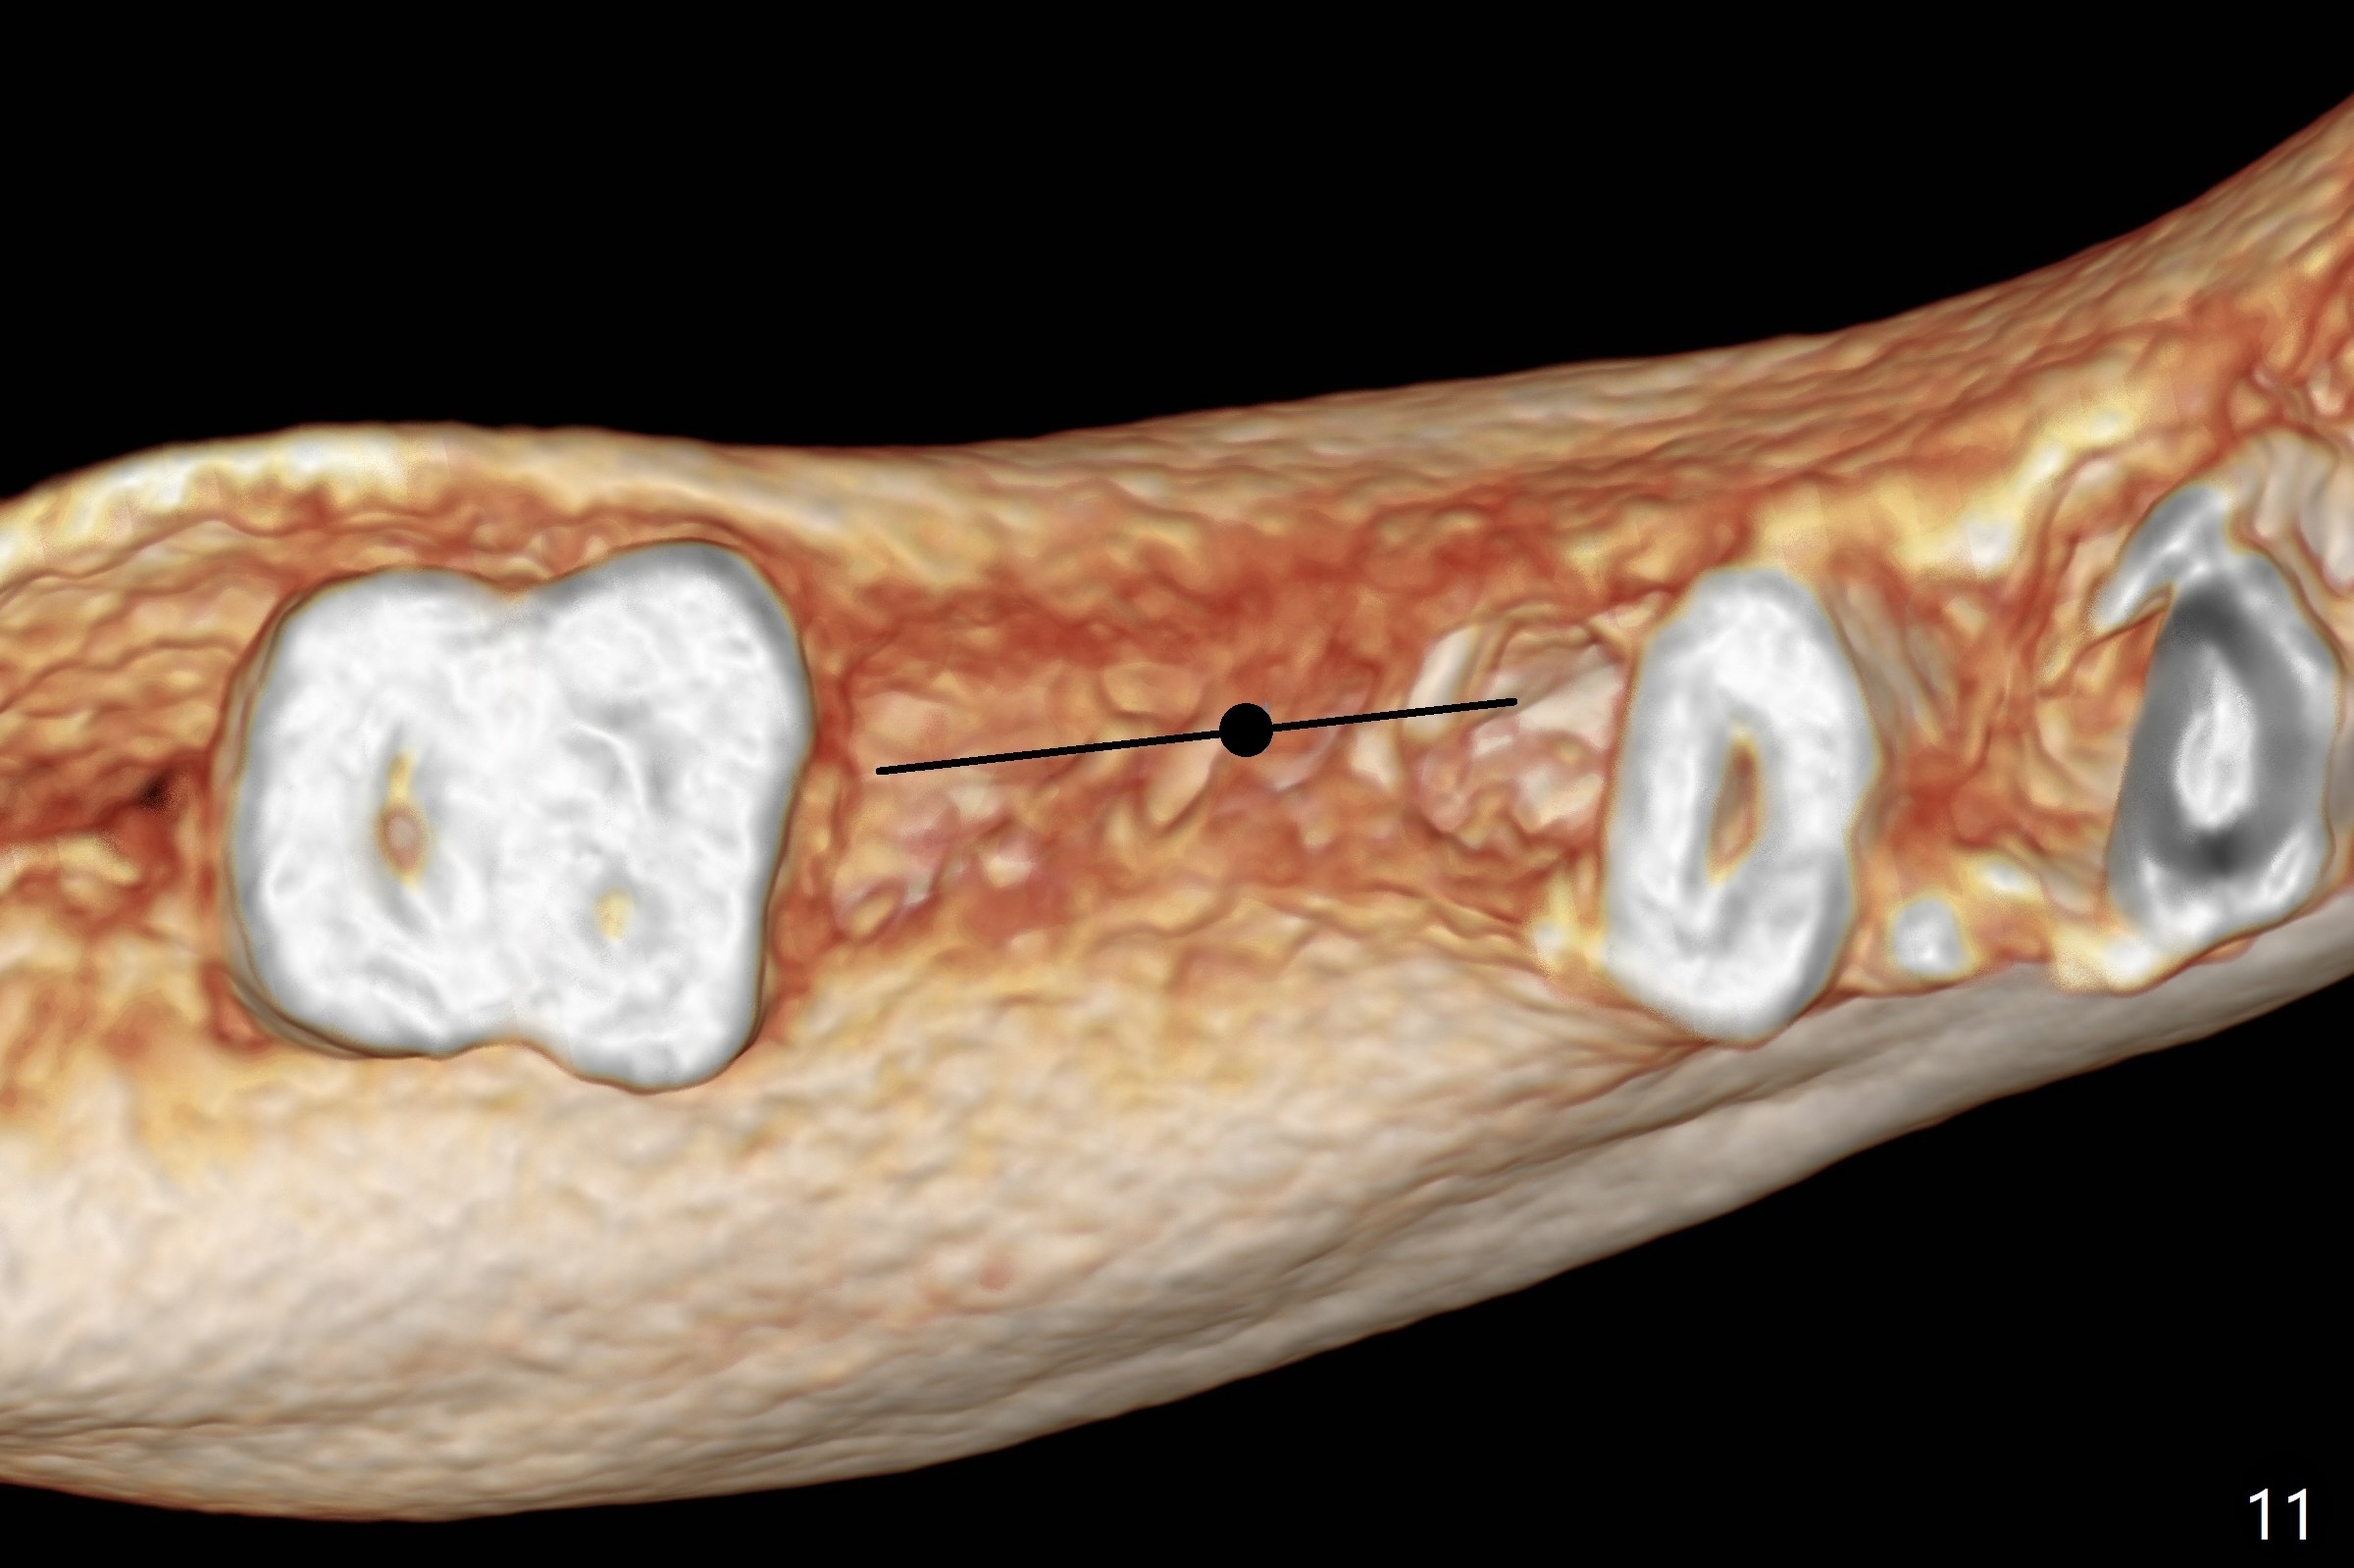

The ridge at #30 is narrow (~ 4 mm buccolingual and ~7 mm mesiodistal, Fig.8). A 4x11.5 mm will be placed. Impression will be taken for guides for #28 and 30. Incision will be made prior to guide seating (Fig.9 occlusal view); initial osteotomy (Fig.10 black circle) will be conducted with guide clockwise (white curved arrow). With removal of the guide, the ridge is split (Fig.11 black line). Osseocondensation drills will be used for ridge expansion with the help of guide (in the middle of the metal sleeve, Fig.12 counterclockwise).